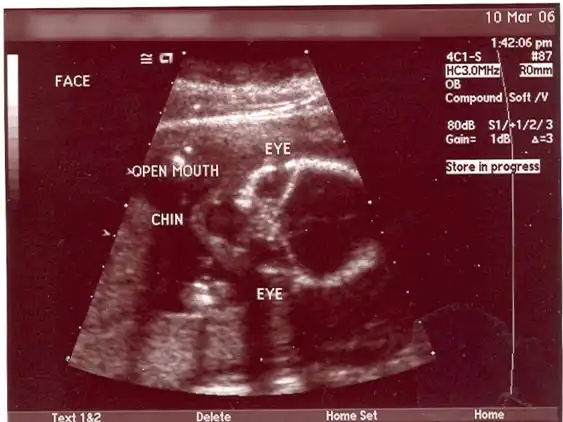

Alien Dad: я чуть не сошел с ума, когда увидел УЗИ своей беременной жены. Я БУДУ ОТЦОМ ИНОПЛАНЕТЯНИНА! Я так горжусь своим пришельцем